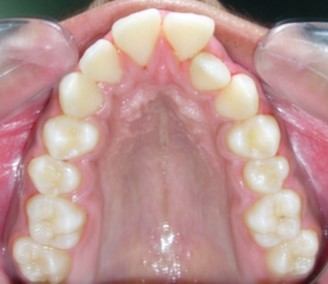

Figure 1g.Pre-treatment intra-oral-Upper occlusal

Pre-treatment intra-oral-Upper occlusal

The maxillary arch was V-shaped with severely proclined and rotated maxillary incisors with a palatally placed 12. The mandibular arch was U-shaped with severe crowding of mandibular incisors, with 43 partially erupted and buccally placed with transpositioned 42 and 43, with 42 mesiolingually rotated, 33 distolingually rotated and 34 distolingually rotated and buccally placed.

Severe increase in overjet and deep bite were both observed. The maxillary midline coincided with the skeletal midline but the mandibular midline was shifted to the right side by 1 mm. Bilateral maxillary posterior crossbite was also observed. On right side the molar relation was Class I and on the left side it was Class II. The canine relation was Class II on the left side and the curve of Spee was increased.